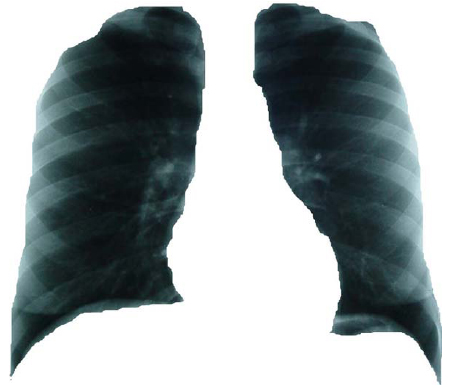

Isla 1: Isla radiopaca a la observación, limitada por los contornos dibujados en la placa detórax del ventrículo y aurícula izquierda, botón aórtico y aurícula derecha, correspondiente a la silueta cardíaca. (Ver Figura 1). Isla 2: Isla radiolúcida a la observación. Está definida por:

Isla 3: Superposición de la isla 1 con la isla

2. Objeto fractal total. Cavidad torácica completa (Ver Figura 3).

Figura 1. Composición de la radiografía de tórax: Isla 1

Figura 2. Composición de la radiografía de tórax: Isla 2.

Figura 3. Composición de la radiografía de tórax: Isla 3.